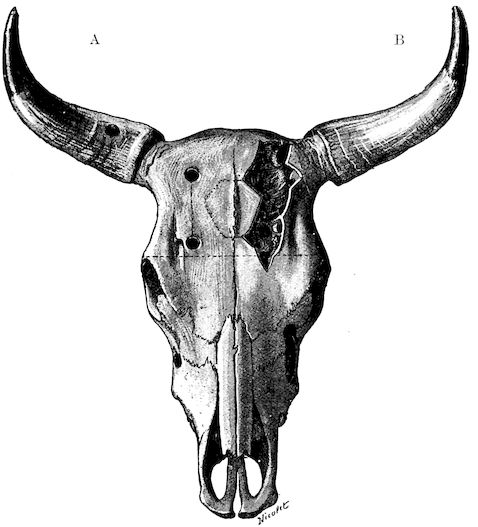

Anatomy of the horns. The horns form organs of defence, and project on either side of the frontal bone at the poll. Each consists firstly of a bony basis generally known as the horn core; secondly, of a horn-secreting membrane; thirdly, of a horny sheath, the horn properly so called.

22(1.) The horn core projecting from the frontal bone does not develop until after birth. About the third month a little prominence appears under the skin, which, as it develops, assumes a conical shape, and may be seen to be covered with a horny substance. In proportion as the horn core grows, there develops within it a cavity which may either be of a simple character or divided by a longitudinal partition. This communicates with the frontal sinus, a fact which explains the collection of pus in the sinuses as a result of injuries to the horns. The sinus of the horn core does not exist in young animals, and is not completely developed before the third or fourth year of life.

Fig. 9.—C, horn; P, modified skin forming the keratogenous membrane; O, horn core, exhibiting a double sinus.

(2.) The horn-secreting membrane is formed by the skin, which undergoes special development around the base of the horn and comes to resemble that of the coronary band, from which the hoof or claw is secreted. The band is about one-fifth of an inch in breadth. The papillæ of the dermis are specially developed at this point, and the epithelium which they secrete eventually forms the horn.

The internal surface of the growing horn is adherent to the horn core through the medium of another tissue formed by a specially differentiated periosteum which is continuous with the periosteum covering the frontal bone. It is not a true periosteum, but a vascular tissue formed of papillary layers analogous to those of the podophyllous tissue of the ox’s claw or horse’s hoof.

This keratogenous membrane receives a rich vascular supply from the arterial circle formed at the base of the horn core by a division of the external carotid, the blood conveyed by which is freely distributed to the enlarged papillæ. The great vascularity of these parts 23explains why lesions of the horns are often followed by such profuse bleeding.

(3.) The horn secreted by the papillæ of the horn band (which is analogous to that of the coronary band of the horse) forms a cone varying in its curve in various breeds. Its base is hollow, and contains little depressions holding the papillæ from which the horn is secreted. From its base up to the end of the horn core the walls progressively increase in thickness. From this point it is solid; in a fully-grown horn the bone does not extend more than one-half or two-thirds of the entire length.

In the adult, the development of the horns varies with different breeds and is affected by sex. In the bull the horns are short, but in the cow and ox long. Short and fine in animals of improved breed like the Durham, they are long and thick in breeds of working oxen.